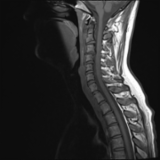

Acute calcific deposit on the enthesis of the longus colli muscle

The severe cervical spine pain prompted an emergency MRI examination, which showed a clear prevertebral inflammatory soft tissue process. On close inspection, a calcific deposit anterior to the dens axis can already be suspected on MRI (especially T2 or axial T1fs Gd+). The calcium depot is only shown very fluffy on X-ray and CT, suggesting an acute stage with precipitation/resorption of the calcific milk.

Therapy is initially conservative. Punctures and surgery of the calcific deposit can be done from endooral.

The longus colli muscle is a less common location of this condition, which should be referred to as HADD or acute calcific deposit. Also affected may be supraspinatus tendon and other tendons of the rotator cuff, extensor carpi radialis tendon, deltoid muscle, or hip adductors.